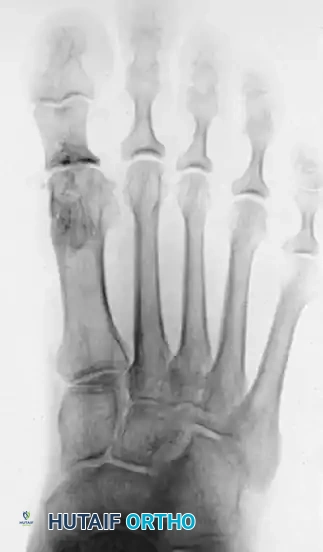

Figure 2: Twelve years post-Keller procedure with excision of the fibular sesamoid. Note the correction of the first metatarsal varus and the maintenance of sufficient joint space to allow a functional range of motion.